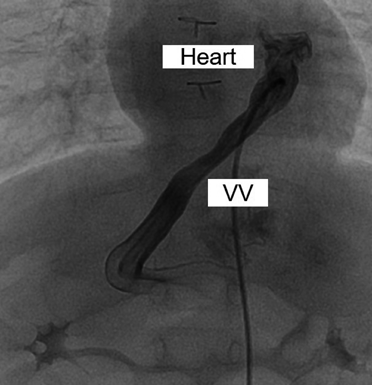

Fig. 3 Abdominal echographic finding of the unligated vertical vein (VV) draining the left-sided atrium on postoperative day 11

VV, vertical vein.

術後経過

術直後は房室接合部頻拍や経時的な肺血流過多によって循環不安定であったが,術後4日目に肺動脈の追加絞扼を行うことで安定した.同日,肺動脈追加絞扼前の採血で肝逸脱酵素の上昇(AST 985U/L, ALT 359U/L)を認め,術後6日目にかけてAST 1000U/L, ALT 450U/Lまで上昇した(Fig. 2).術後7日目に閉胸したが,術後8日目より凝固能異常(APTT 110秒,PT-INR 2.78,フィブリノーゲン60 mg/dL以下,AT-III 21.1%)を認め,新鮮凍結血漿の投与を5日間要した.術後11日目に腹部エコーを施行したところ,門脈から遺残垂直静脈を介して心房に流入する血流を認め,PSSと診断した(Fig. 3).心エコー上,左右房室弁逆流はなかった.術後13日目には高アンモニア血症(NH3 154 µg/dL)を認め,術後26日目までNH3 100台µg/dLで推移した.術後25日目に低血糖(45 mg/dL)を認めたが,持続経腸栄養とグルコース持続投与を行って改善を得た.以後,血液データはいずれも正常化して,術後47日目にCardiac ICUを退室した.術後60日目に造影CT検査を行い,右肺静脈が心房開口部でやや狭いものの,修復した肺静脈は両側とも開存していることや,静脈管が閉鎖していることを確認し,術後69日目に退院となった.